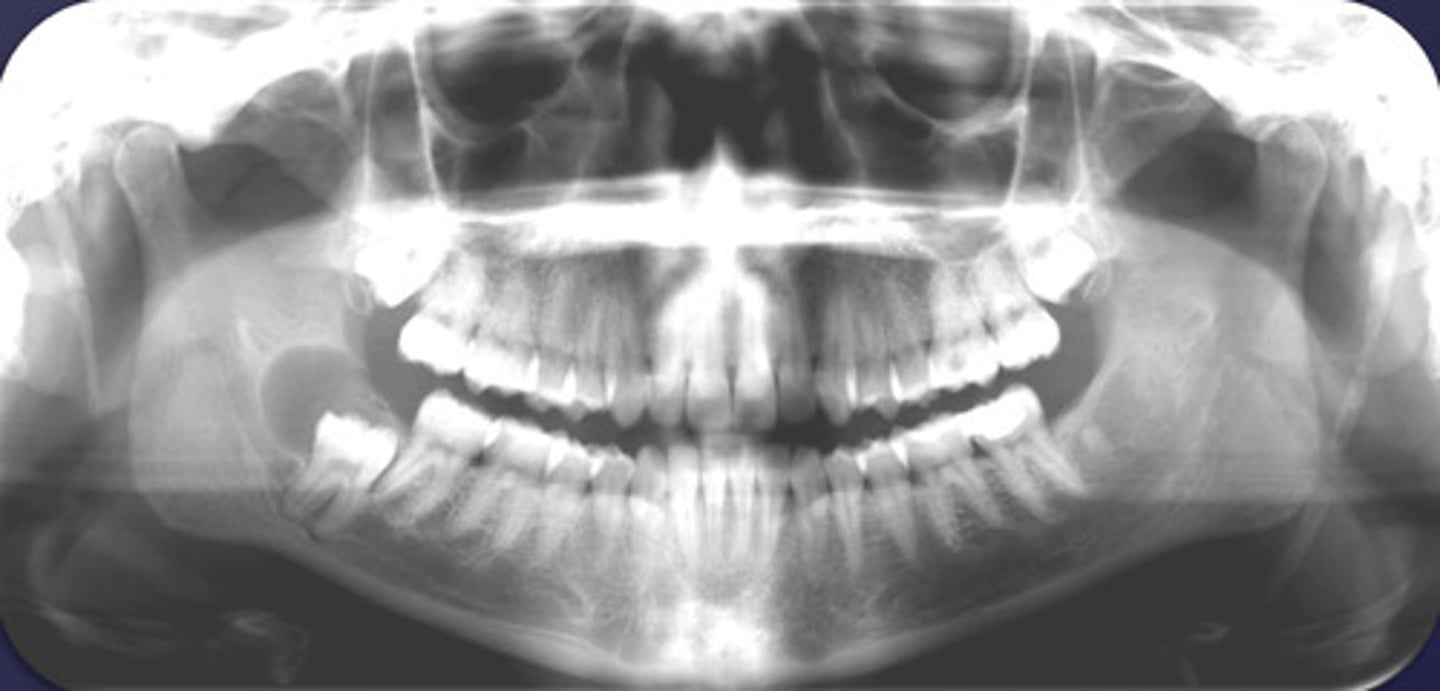

How would you describe the lesion?

- Well-defined corticated multilocular radiolucency in the right ramus

- Mandibular body causing root resorption

- Expansion and thinning of anterior wall of ramus, coronoid process, inferior border of mandible

- Displacement of the inferior alveolar canal

What category would this lesion be part of?

Benign

What would be a differential diagnosis for this lesion?

- Ameloblastoma

- OKC